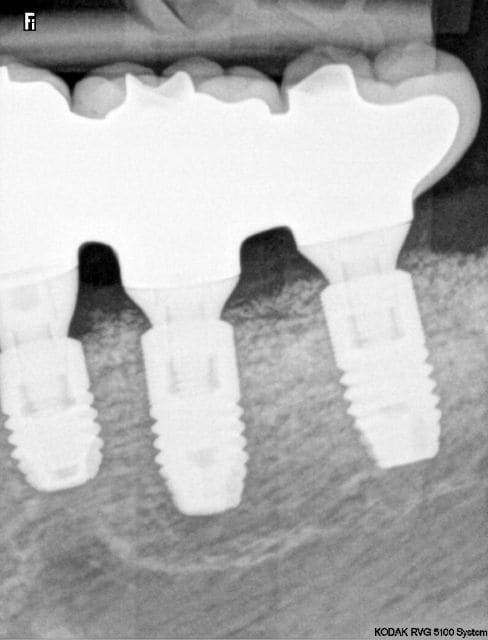

je suis débutant en implanto mais,

-Cà ne pose pas problème l'aspect granuleux de l'os crestal vu sur la rx?

-La 4 a été solidarisée au reste?

BucaR écrivait:

---------------

> je suis débutant en implanto mais,

> -Cà ne pose pas problème l'aspect granuleux de l'os crestal vu sur la rx?

> -La 4 a été solidarisée au reste?

L'aspect granuleux ce sont des des granules de BIo-oss, je pense pas que cela pose problème.

non bien sur sûr la 4 n'est pas solidarisée.